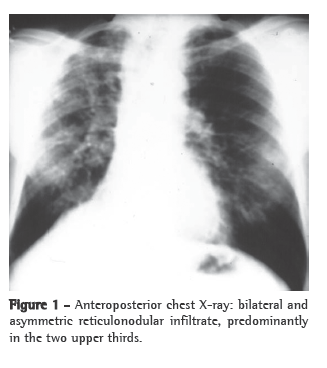

A HRCT scan (Figure 2) can reveal nodules, ground-glass opacities, tree-in-bud pattern, acinar lesions, parenchymal bands, peribronchovascular interstitial thickening, cavities, reticular pattern, "reversed halo" sign, scar-related emphysema and traction bronchiectasis.(8,9)